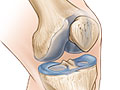

La manera más sencilla de describir la artritis es decir que se trata del desgaste del cartílago de las articulaciones. Este tejido amortiguador es firme, grueso y resbaloso. Cubre y protege el extremo de los huesos, donde se juntan para formar la articulación.

Con la artritis, hay cambios en el cartílago que hacen que este se deteriore. Cuando se deteriora, se genera fricción entre los huesos, lo que causa daño y dolor. Los expertos no saben por qué ocurre ese deterioro en el cartílago. Pero el envejecimiento, las lesiones en las articulaciones, el sobrepeso y la genética podrían ser una parte de la razón.

La osteoartritis se produce cuando los cambios en el cartílago hacen que este se deteriore y se desgaste. Cuando se deteriora el cartílago, se genera fricción entre los huesos, lo que causa daño y dolor. Los expertos no saben por qué sucede esto. Sin embargo, existen factores, como el envejecimiento, la lesión de las articulaciones, el sobrepeso y la genética que podrían aumentar su riesgo.

La osteoartritis se produce cuando el cartílago que amortigua las articulaciones se deteriora y se desgasta. Cuando esto sucede, se genera fricción entre los huesos, lo que causa daño y dolor. En la mayoría de los casos, lleva años que el cartílago se deteriore.